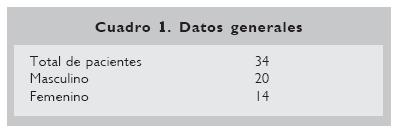

Se incluyeron 34 pacientes con microtia, 20 del sexo masculino y 14 del sexo femenino (Cuadro 1), con una edad promedio de 9.5 años (n =7–12 años). Se incluyeron 31 pacientes con microtia unilateral y tres con microtia bilateral. Dentro de la presentación clínica unilateral, no se encontró diferencia en la presentación derecha (n =16) o izquierda (n =15) (Cuadro 2).